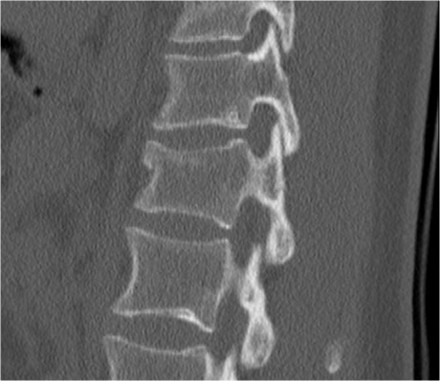

The images show a compression fracture.

All we see is a cortical disruption in the upper anterior wall of the vertebral body and slight loss of height ventrally.

The posterior vertebral cortex is intact.

The sagittal reformatted image also shows the cortical disruption.

Notice that on a 2.5mm axial slice you can miss these fractures.

You have to look at the thin slices to detect such a subtle fracture.

It is very common to see more fractures on imaging with CT and MRI than on the radiographs.

In this case the CT shows 2 fractures and the MRI shows 3 fractures.